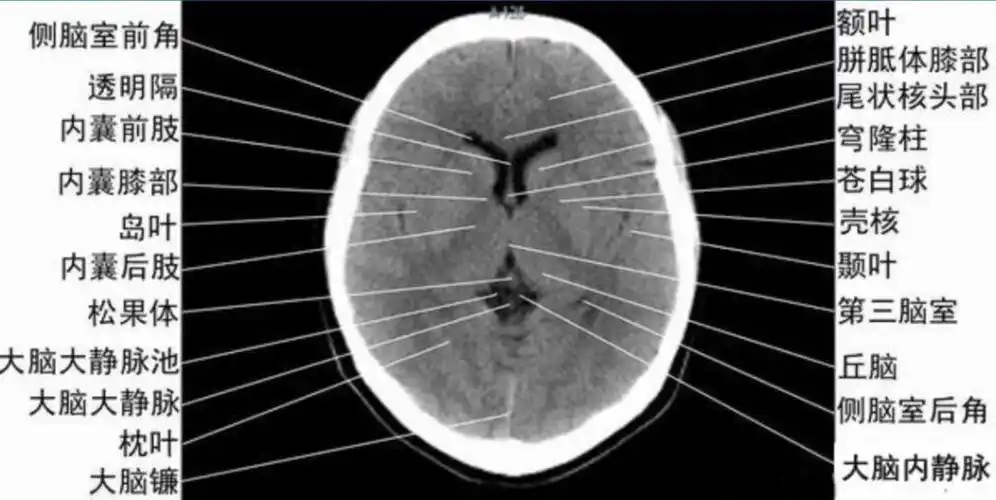

读懂头颅ct并不难教你成为读片小能手